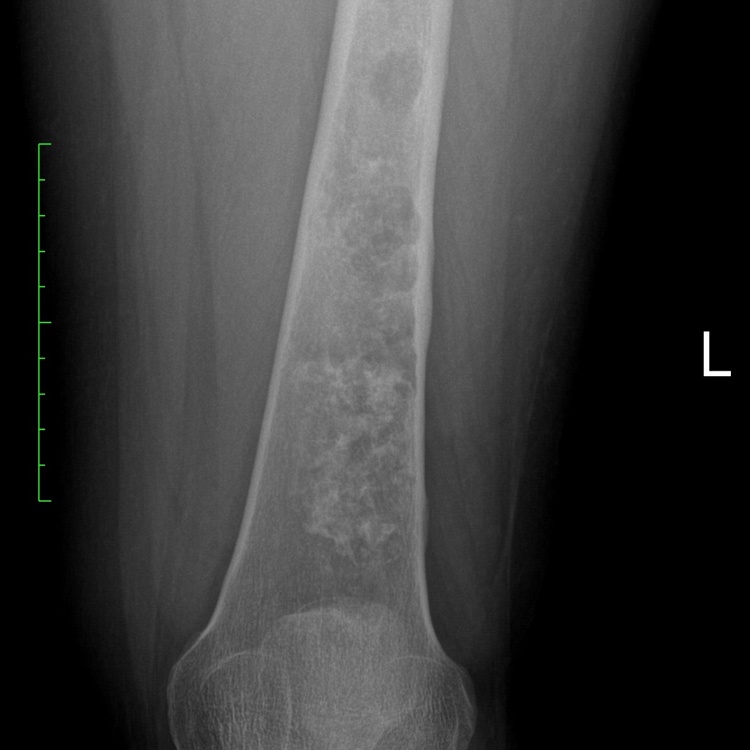

Radiographic imaging is used to help form a diagnosis. These include X-Ray, MRI, CT and Bone Scans.

- • The work-up is often consist of a physical examination, X-rays, CT scans, MRI, and sometimes bone scans are required. CT scans can be used to check for subtle mineralization that may help with the diagnosis